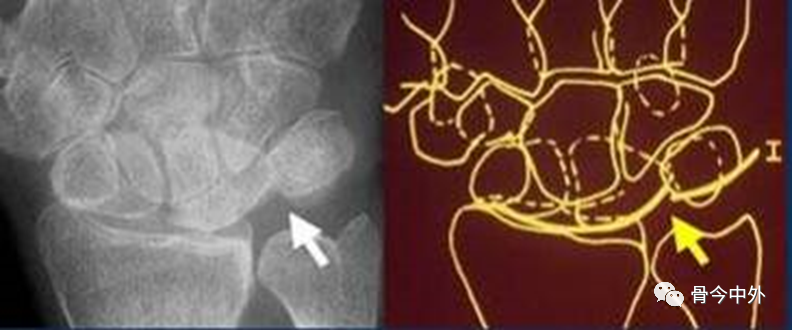

图17

腕骨弧线中断;弧线中断提示骨折或韧带断裂导致的半脱位或脱位。上图显示弧线Ⅰ在月骨-三角骨关节处的中断。